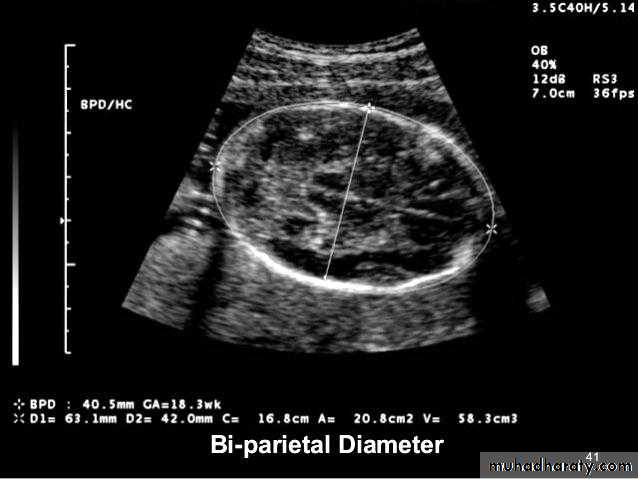

BPD together with head circumference (HC), abdominal circumference (AC), and femur length (FL) are computed to produce an estimate of fetal weight. In the second trimester this may be extrapolated to an estimate of gestational age and an estimated due date (EDD) .

The BPD should be measured on an axial plane that traverses the thalami, and cavum septum pellucidum. The transducer must be perpendicular to the central axis of the head, and thus the hemispheres and calvaria should appear symmetric.